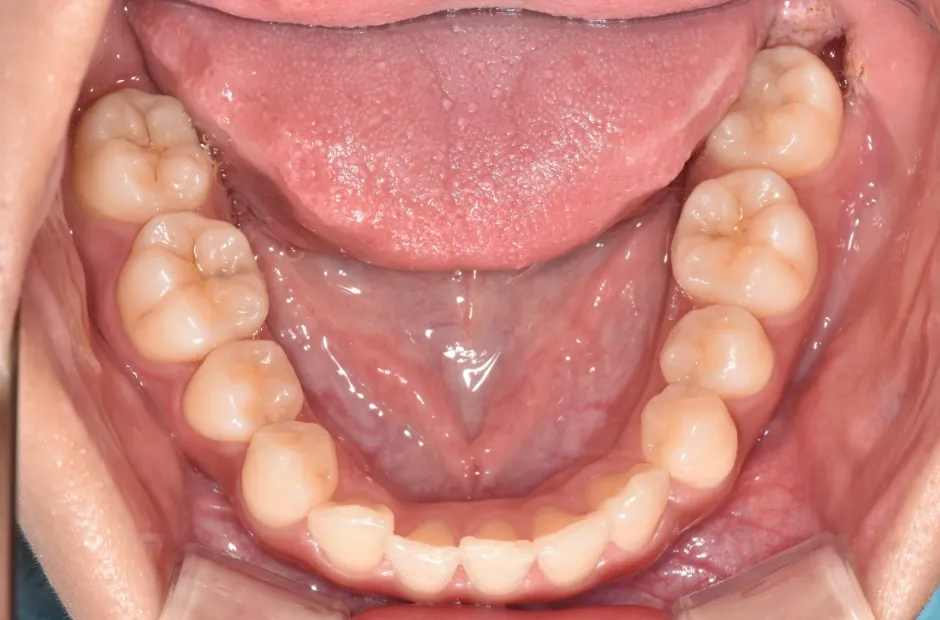

叢生

| 診断名・主訴 | 叢生 |

|---|---|

| 年齢・性別 | 43歳・女性 |

| 治療期間・回数 | 2年7か月 27回 |

| 治療に用いた主な装置 | 舌側矯正 |

| 抜歯部位 | 両顎4,4 |

| 治療費 | 100万円(税抜) |

| リスク・副作用 | 装置による違和感・疼痛・歯肉退縮・歯根吸収・虫歯のリスクなど |

治療前

治療中

治療後